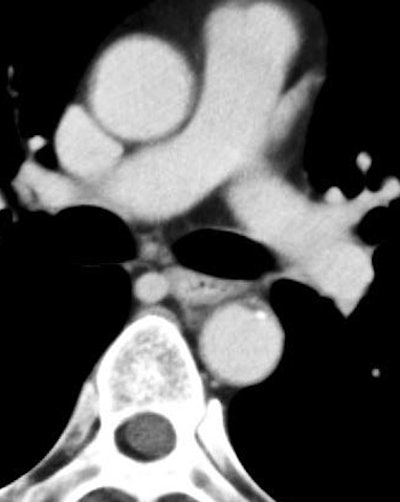

![]() |

| Arterial-phase image of 60-year-old male with T1b esophageal cancer. The tumor is clearly enhanced on the arterial phase (arrow). The lesion was T1b at surgery. All images courtesy of Dr. Shigeaki Umeoka. |